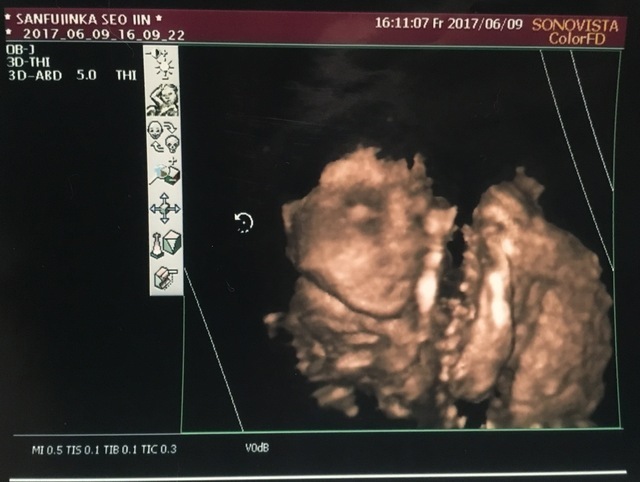

23週5日(23w5d・男の子)|さんちゃん43 さん(29歳)

初めて3Dエコーを撮りました。最初は腕で隠して顔を見せてくれなかったけど、再チャレンジで微笑んでくれました。この日に性別も判明!

「次は検診一緒に行くから」って張り切ってるパパの期待に反して、パパがついてきた検診ではまだ一度も顔を見せてくれません。